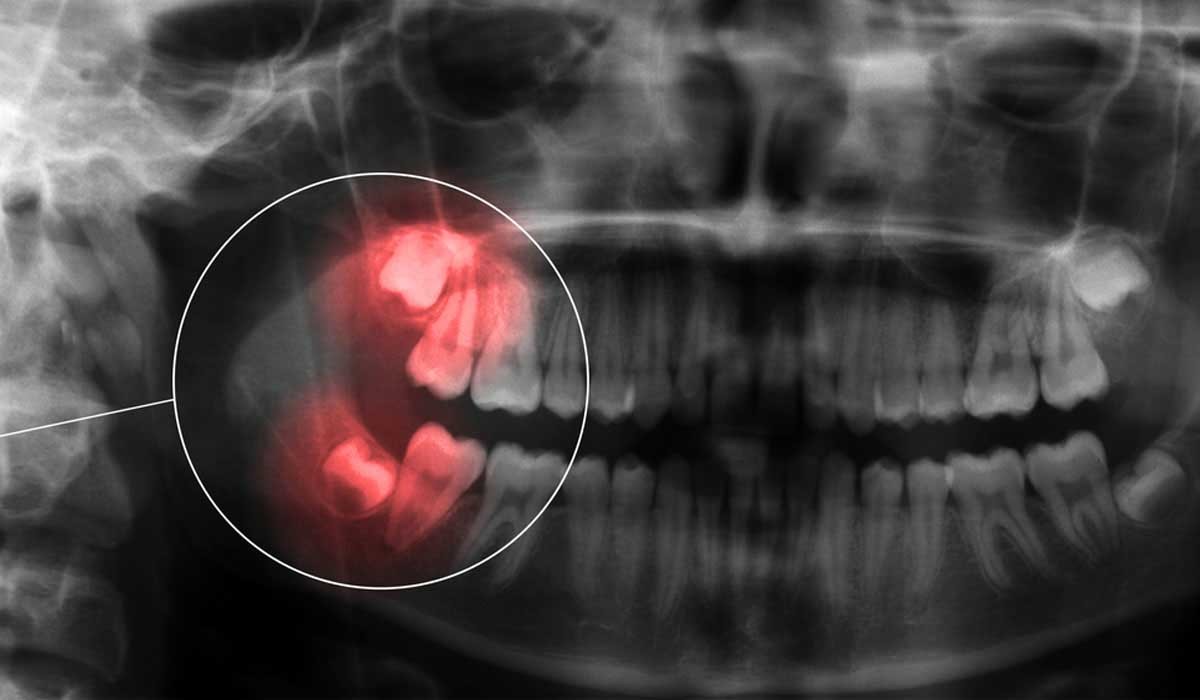

Endoguide nada mais é do que o acesso guiado ao sistema de canais do dente. Uma solução fantástica para resolução de casos complexos. Por meio de tomografia computadorizada, escaneamento digital, prototipagem, impressão 3D torna-se possível acessar canais calcificados com maior segurança e conforto.

Indicado em casos com calcificações severas, nos quais mesmo com microscópio e toda experiência do operador são difíceis de localizar e acessar, especialmente aquelas que ultrapassam o terço cervical, ou seja a porção inicial da raíz.

Excelente solução também para remoção de pinos dentro do canal do dente, especialmente pinos pré-fabricados, de forma segura e conservadora evitando desgastes desnecessários, desvios e até perfurações.

A radiologia odontológica e imaginologia é a especialidade que, provavelmente, mais se relaciona com as demais disciplinas dentro da odontologia, sendo uma ferramenta essencial para diagnóstico, planejamento e acompanhamento no tratamento de doenças bucais. Como exemplos podemos citar as radiografias periapicais, panorâmicas, tomografia computadorizada, ressonância magnética, entre outros dentro de sua especificidade.

A Tomografia Computadorizada possibilita aquisição quase imediata da imagem sem etapa de processamento químico, com visualização de estruturas em três dimensões. O tratamento e processamento das imagens são feitas no computador, empregando técnicas que podem influenciar no resultado diagnóstico das imagens, possui espaço reduzido para armazenamento das imagens, além de facilitar no compartilhamento das mesmas.

Tomografia Computadorizada Cone Beam (CBCT), foi desenvolvida especialmente para a Odontologia, com melhor nitidez, limitação do feixe de raios X em forma de cone, menor tempo de varredura e menor dose de radiação, menos artefatos de movimentos de paciente, aparelho mais compacto, facilitando o paciente ficar em pé ou sentado, melhorando o conforto e a precisão nos resultados dos exames.